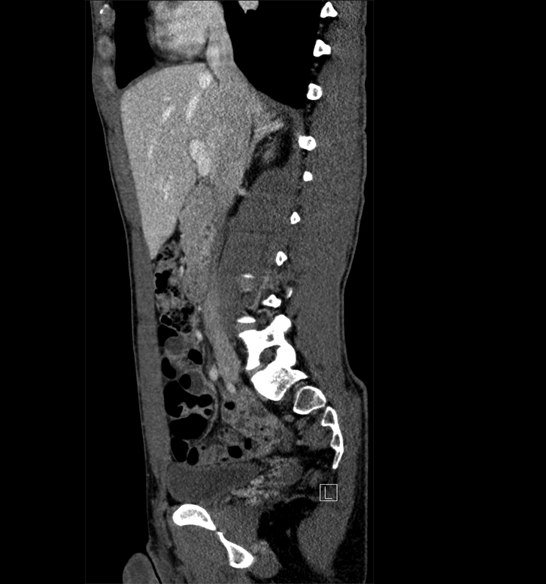

Body

Covers abdominal CT anatomy.